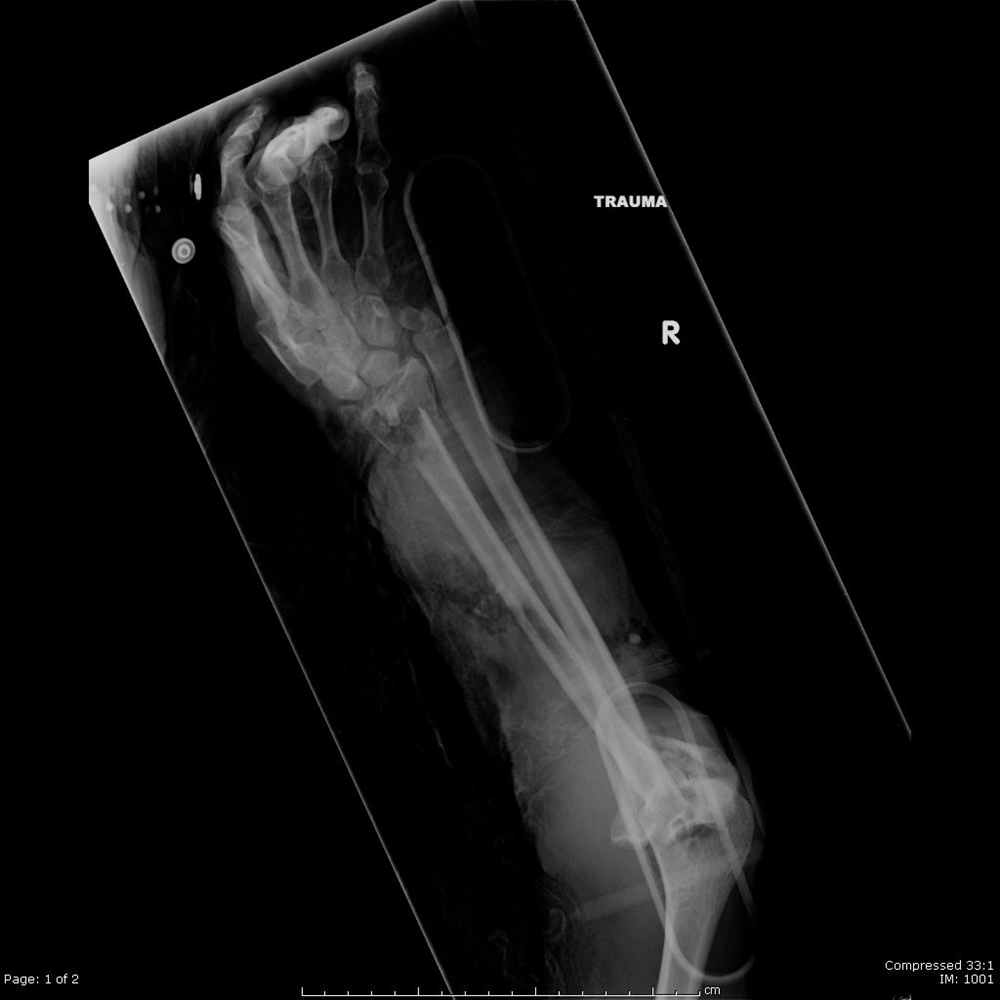

Radius Ulna Fracture Orthobullets . — ulnar styloid fracture occurs together with distal radius fracture that has high degree of initial displacement. ulnar styloid fracture is commonly associated with distal radius fracture (drf). The ulnar styloid plays a crucial role in the. — distal radius fractures are the most common orthopaedic injury and generally result from fall on an outstretched hand. distal radius fractures are the most common upper extremity fracture and account for over a sixth of all fractures seen in emergency. — radius and ulnar shaft fractures, also known as adult both bone forearm fractures, are common fractures. — evaluate druj and elbow for associated injuries (galezzi, monteggia fractures) check compartment pressure.

— evaluate druj and elbow for associated injuries (galezzi, monteggia fractures) check compartment pressure. ulnar styloid fracture is commonly associated with distal radius fracture (drf). distal radius fractures are the most common upper extremity fracture and account for over a sixth of all fractures seen in emergency. The ulnar styloid plays a crucial role in the. — ulnar styloid fracture occurs together with distal radius fracture that has high degree of initial displacement. — distal radius fractures are the most common orthopaedic injury and generally result from fall on an outstretched hand. — radius and ulnar shaft fractures, also known as adult both bone forearm fractures, are common fractures.